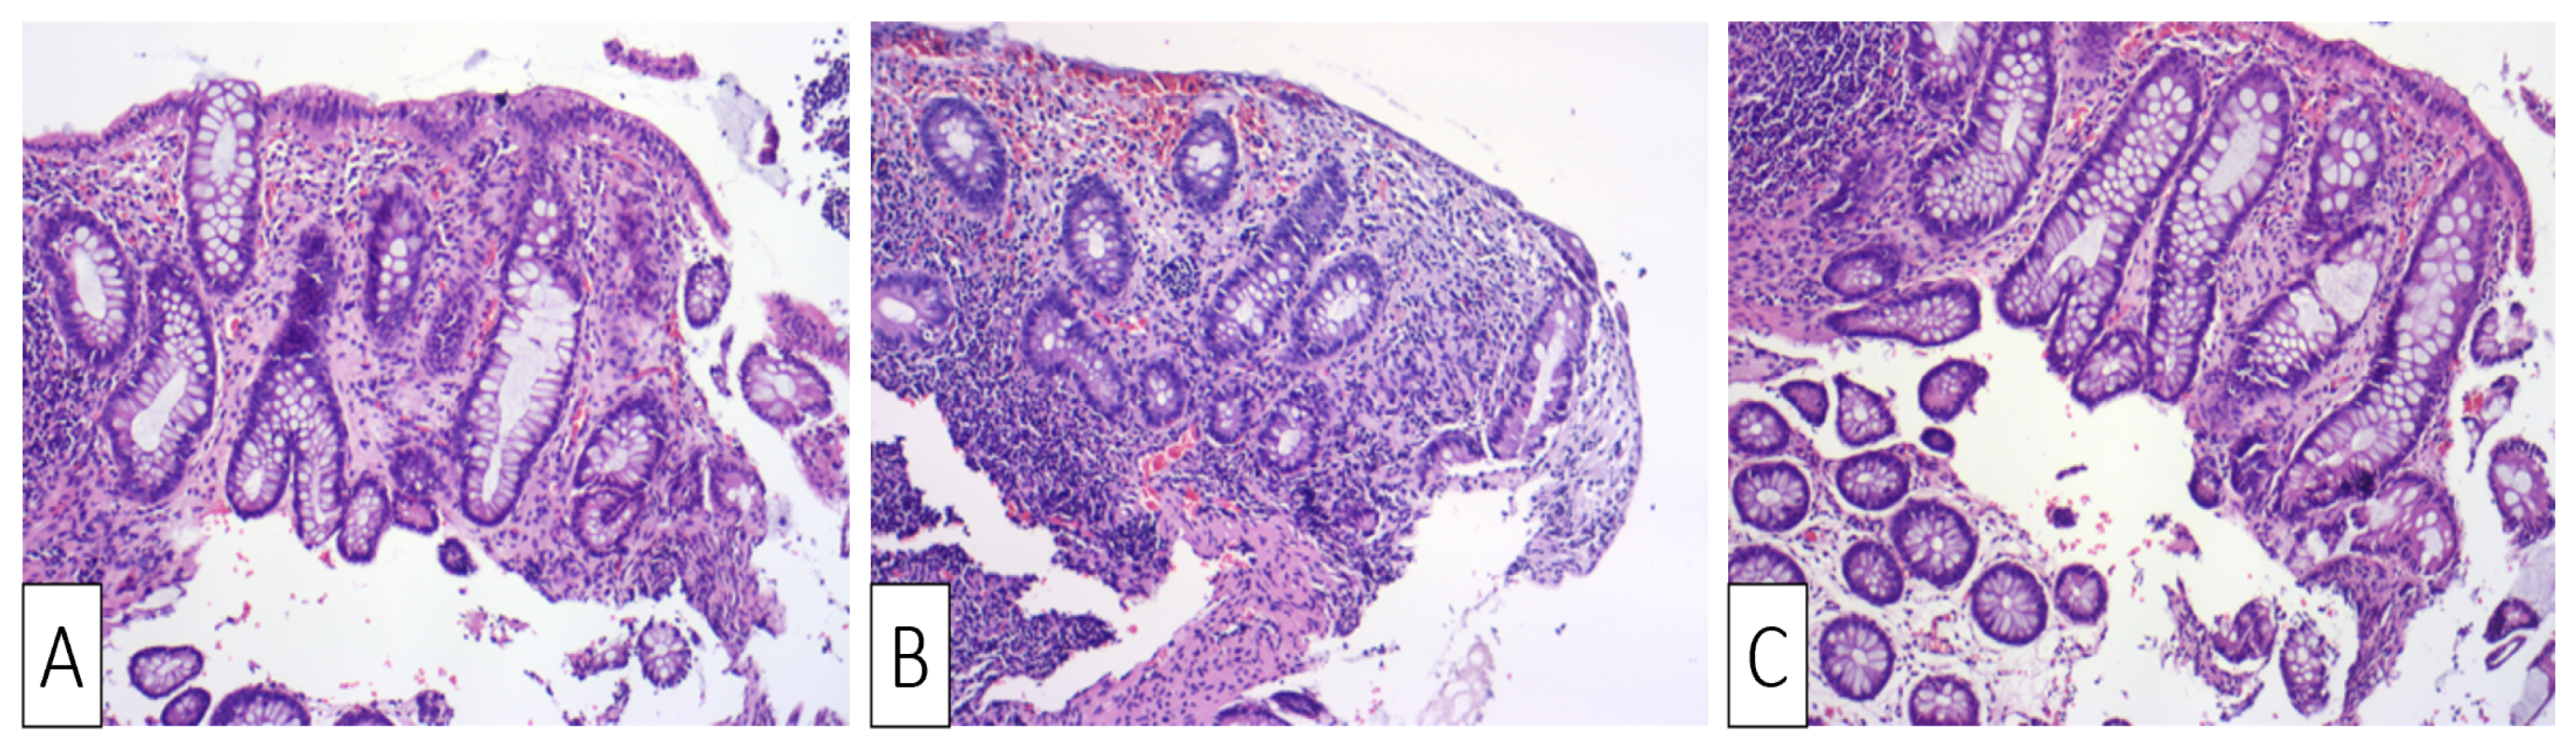

| Our patient | Male, 30 | Colicky left lower quadrant abdominal pain and bloody diarrhea | Negative fecal culture, positive toxins A, B, and GDH | Idiopathic | Several superficial longitudinal ulcerations with luminal narrowing spanning from sigmoid to the descending colon | Desquamation of superficial epithelium with focal necrosis, loss of superficial glands, edematous and necrotic lamina propria | Oral Vancomycin, symptoms resolved within two days of hospitalization |

| Okada et al., 1997 [30] | Male, 52 | Crampy lower abdominal pain followed by bloody diarrhea | Positive fecal culture and strongly positive D-1 toxin | Three-day use of Cefteram for gingivitis | Edematous mucosa with multiple longitudinal shallow ulcers, erosions, and luminal narrowing | Desquamation of superficial epithelium with crypt degeneration, fibrinous exudates in lamina propria, and mild neutrophilic infiltration | Supportive treatment, symptoms resolved by third day of hospitalization |

| Veroux et al., 2007 [31] | Female, 42 | High fever, diffuse abdominal pain with tenderness and bloody diarrhea | Positive toxins | Two weeks after renal transplant; CDI colitis was complicated by CMV colitis | Edematous mucosa with patchy erythema and longitudinal ulceration | Mucosal inflammation, hemorrhage, with leukocytoclastic vasculitis and lymphoplasmacytic perivascular infiltrate | Metronidazole and oral Vancomycin for seven days with no improvement; patient underwent subtotal colectomy but passed away two weeks later |